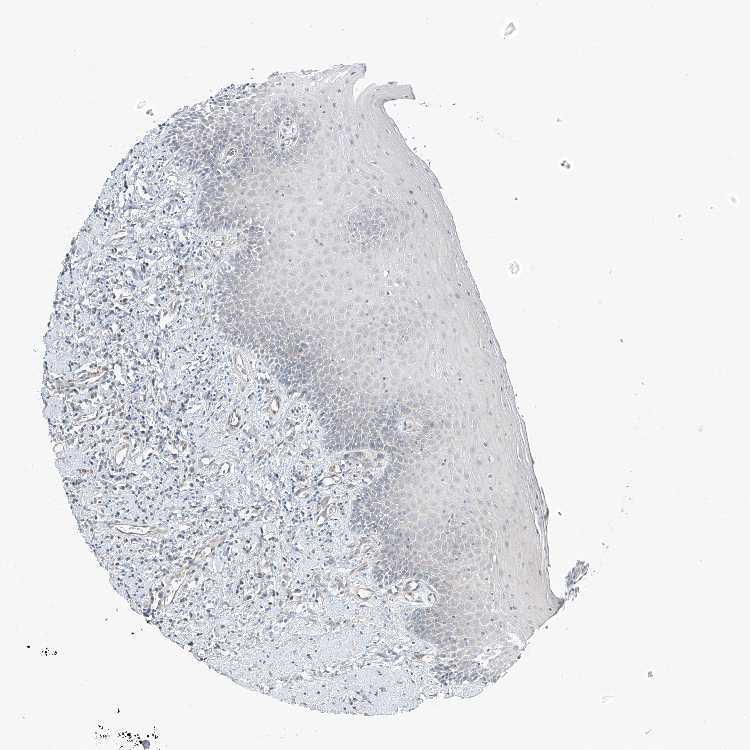

TISSUE PRIMARY DATA ORAL MUCOSA Show tissue menu

ORAL MUCOSA - Antibody stainingi

Antibody staining in the annotated cell types in the current human tissue is reported as not detected, low, medium, or high, based on conventional immunohistochemistry profiling in selected tissues. This score is based on the combination of the staining intensity and fraction of stained cells.

Each image is clickable and will lead to virtual microscopy that enables deeper exploration of all samples and also displays staining intensity scores, fraction scores and subcellular localization as well as patient and tissue information for each sample.

Antibody HPA034659

Squamous epithelial cells Not detected